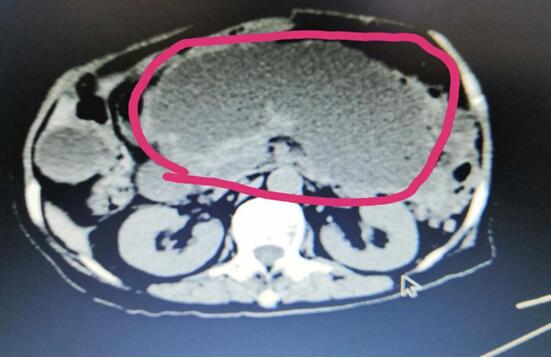

病例A

患者A,女,72歲,1年前因急性出血壞死性胰腺炎,曾行腹腔鏡下壞死胰腺組織清創(chuàng)+外引流術(shù),術(shù)后出現(xiàn)急性胰腺假性囊腫,囊腫越來越增大,以至于病人不能做下蹲和彎腰動作,給生活造成極大不便。本次患者因急性腹痛入院,入院診斷為:胰腺巨大假性囊腫并發(fā)出血,重癥胰腺炎清創(chuàng)術(shù)后。

(術(shù)前腹部CT顯示胰腺巨大假性囊腫)

患者于2020年2月24日,在3D腹腔鏡下行胰腺假性囊腫-空腸Rou-Y吻合內(nèi)引流術(shù)。術(shù)中醫(yī)生克服腹腔極其嚴(yán)重腹腔粘連等困難,經(jīng)胃結(jié)腸韌帶間隙入路,于囊腫最低位置開窗,吸盡囊液,清洗干凈囊腔,止住囊內(nèi)出血,完成與空腸吻合。